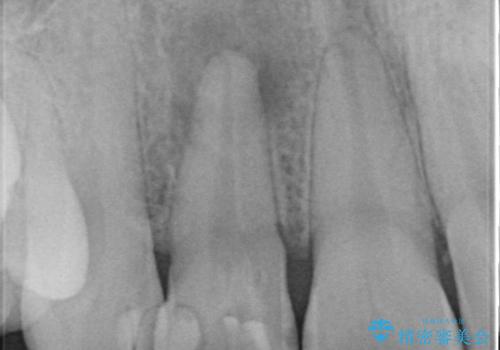

- 前歯が痛いことを主訴に来院されました。

顕微鏡やラバーダムを使用した根管治療を行ってくれる病院を探していたそうです。

根管治療を含め、オールセラミッククラウンにて修復治療を行っております。

当院の根管治療は100%ラバーダムを使い無菌的な処置に配慮して行っております。